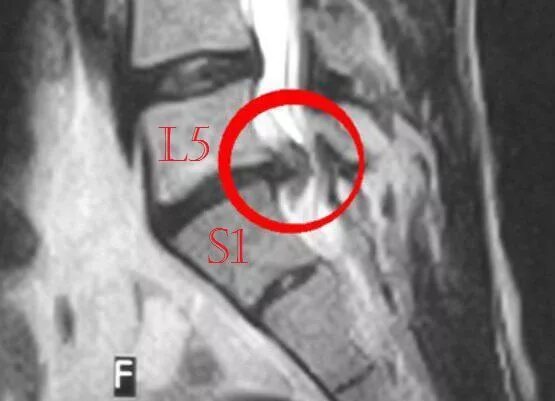

Грыжа 4 5